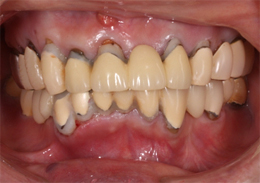

上顎のALL-ON-4(ノーベルクリニシャンを使用したフラップレス術式)

- 主訴

- 歯周病で歯がグラグラするので噛めない

- 治療内容

- 上顎に残存していた歯を抜歯。歯肉の治癒後にフラップレス手術にてインプラント埋入を行い、その場で準備してあった上顎上部構造を仮歯として、ねじ固定式で装着

- 治療費用

- 上顎ALL-ON-4:4,000,000円(税別)

- 治療期間

- 6ヶ月